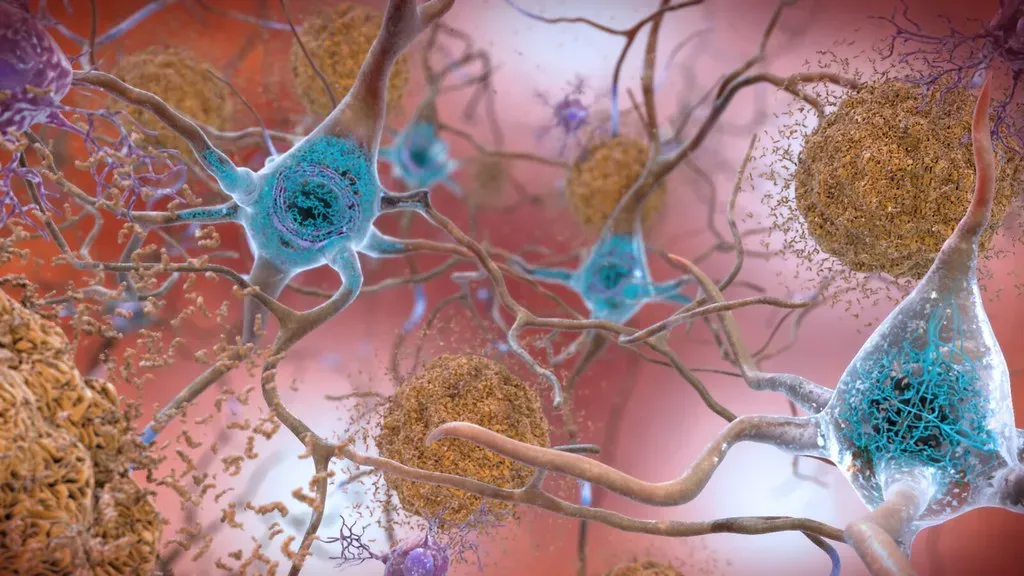

Long-Term Memory Can Form Without Short-Term Memory as a Middleman

For years, the scientific consensus was relatively clear: a memory had to pass through short-term memory before it could settle into long-term storage. It was like a waiting room you couldn’t skip. Well, that model has now been turned on its head. Researchers have discovered a new pathway to forming long-term memories in the brain. Their work suggests that long-term memory can form independently of short-term memory, a finding that opens exciting possibilities for understanding memory-related conditions.

Researchers from Max Planck Florida Institute for Neuroscience discovered a new pathway to forming long-term memories in the brain. Their work suggests that long-term memory can form independently of short-term memory, a finding that opens exciting possibilities for understanding memory-related conditions. This study has changed the model of how memories are formed in the brain. Significant scientific advances often come after previous models of understanding are overturned. It’s a reminder that just when we think we’ve got the brain figured out, it goes ahead and rewrites the rulebook entirely.